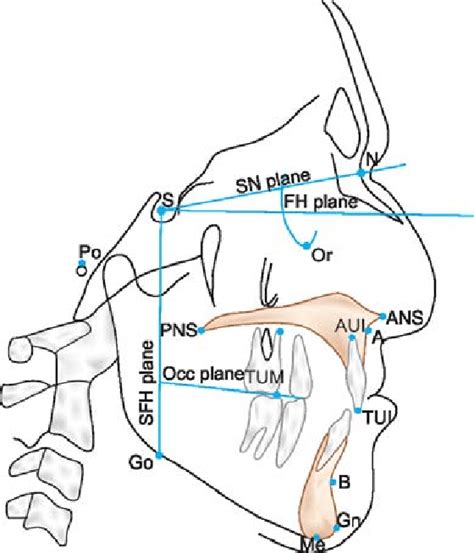

در این عکس، نقاط آناتومیک مشخصی توسط متخصص تعیین شده و بر اساس خطوط و زوایا تحلیل میشوند. این اطلاعات برای تشخیص دقیق و طراحی طرح درمان لازم است.

۲. علامتگذاری نقاط آناتومیک

نقاط خاصی روی عکس مشخص میشوند که مبنای اندازهگیری هستند.

۳. اندازهگیری زوایا و فواصل

زاویهها و خطوط مهمی مانند:

SNA

SNB

ANB

و شیب دندانهای بالا و پایین محاسبه میشود.

۱. موقعیت فکها نسبت به جمجمه

تشخیص جلو یا عقب بودن فکها.

۲. زاویه و موقعیت دندانها

ارزیابی بیرونزدگی یا عقببودگی دندانها.

۳. نوع الگوی رشد صورت

عمودی، افقی یا طبیعی.